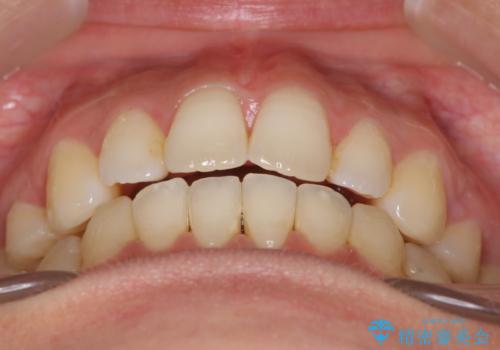

出っ歯で口が閉じずらい ワイヤーによる抜歯矯正

- 出っ歯で口が閉じずらくて、前歯でものかが噛み切れないとのことで来院されました。

上顎の前歯が前方に傾斜して、下顎の前歯と接触していない状態でした。

上顎の前から4番目の歯を両側抜歯して前歯を後方に移動させる計画としました。

前歯がしっかり下がることで、上下の前歯があわさり食事もしやすくなったと言っていただきました。